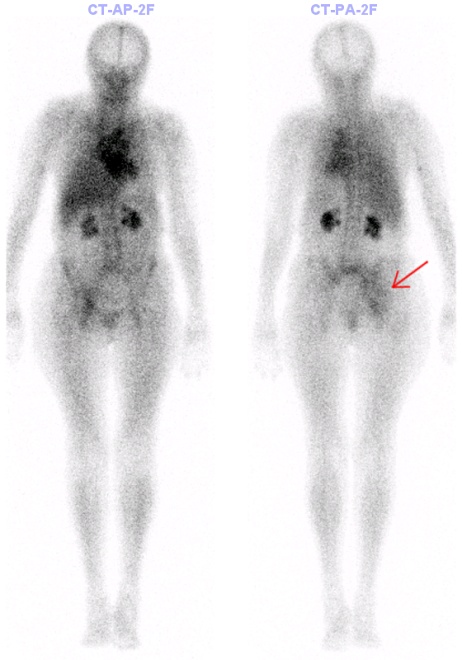

/Obr. č. 2 - Celotělový scan, fáze blood-poolu/

/Obr. č. 3 – Celotělový scan, kostní fáze/

Ve fázi blood poolu patrné rozsáhlé splývavé ložisko zvýšené perfuze, směřující od pravého SI kloubu kaudálně do acetabula pravého kyčelního kloubu - výrazněji dorzálně. Doporučeno vyšetření magnetickou rezonancí k bližší dif. dg – zánětlivá etiol? Tu etiol?

V kostní fázi vyšetření v těchto lokalitách jen mírně zvýšená kostní přestavba. Výrazněji zvýšená kumulace v oblasti S1 - fraktura? Meta?